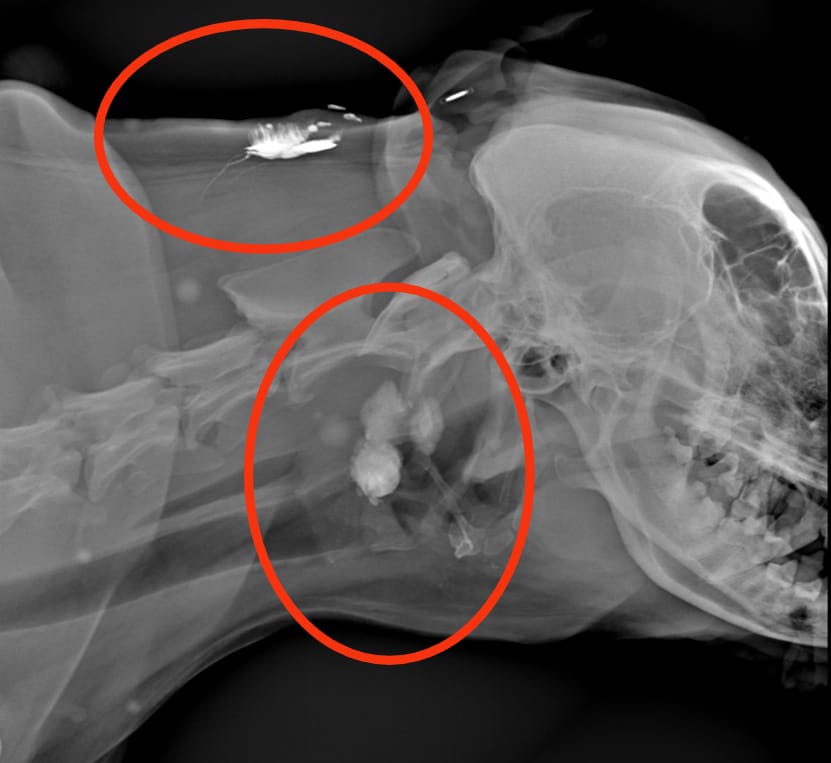

Il linfonodo regionale, ovvero il linfonodo che drena la linfa di quella determinata regione corporea, viene ricercato tramite l’inoculo perilesionale di una sostanza visibile all’esame radiografico (radiopaco). Dopo aver iniettato il mezzo di contrasto, sono state eseguite delle radiografie dopo 3, 6, 9 e 12 minuti: da queste è stato possibile osservare diversi “percorsi” del mezzo di contrasto che si portavano verso il linfonodo prescapolare.

E’ tutto pronto per la chirurgia, ma prima è necessario un ulteriore accertamento: si inietta ai 4 punti cardinali di entrambi i noduli 0,1 ml per sede di blu di toluidina sterile, il colorante verrà drenato verso il linfonodo e lo colorerà di blu, in questo modo si avrà un’ulteriore conferma che si tratti del linfonodo regionale o linfonodo sentinella, e inoltre sarà più facilmente visibile durante la chirurgia.